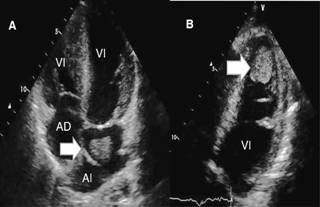

El ecocardiograma reveló anillo supravalvular mitral semejante a cor triatriatum, pero sin condicionar obstrucción, sobre el cual se observó masa sugestiva de trombo de 35 x 22 mm.

Se halló trombo en aurícula izquierda que se debe a la velocidad lenta del flujo sanguíneo auricular por la obstrucción que condiciona la membrana supravalvular mitral (Figura 2A), además de imagen sugestiva de trombo de 24 x 18 mm en ápex de ventrículo izquierdo provocado por acinesia de los segmentos apicales del ventrículo izquierdo, condicionando estasis sanguínea y presencia de arritmia por el síndrome de preexcitación, con la consecuente formación del trombo ventricular (Figura 2B). La válvula mitral estenótica con área valvular de 1.2 cm2; tiempo de hemipresión de 185 ms y con morfología en paracaídas (Figuras 3 A y B). Se detectó obstrucción subaórtica que condiciona estrechamiento del tracto de salida del ventrículo izquierdo y válvula aórtica bivalva con estenosis severa; con gradiente medio de 40 mmHg y velocidad máxima de 4 m/seg; presión sistólica de la arteria pulmonar de 70 mmHg; además de hipoplasia del anillo aórtico y arco aórtico hipoplásico con coartación aórtica postductal y persistencia de conducto arterioso estimado en 21 mm, corroborado por tomografía (Figuras 4 A y B). En un lapso de cuatro horas la paciente mostró insuficiencia cardiaca refractaria con edema agudo de pulmón, además de múltiples episodios de taquicardia supraventricular y posible desprendimiento de los trombos, ocasionando su deceso.

Figura 2: Ecocardiograma en el que se aprecia en A. Anillo supravalvular mitral y trombo 35 x 22 mm (flecha) intraauricular. En B. Imagen de trombo de 24 x 18 mm en ápex de ventrículo izquierdo (flecha). AD = aurícula derecha; AI = aurícula izquierda; VD = ventrículo derecho; VI = ventrículo izquierdo.